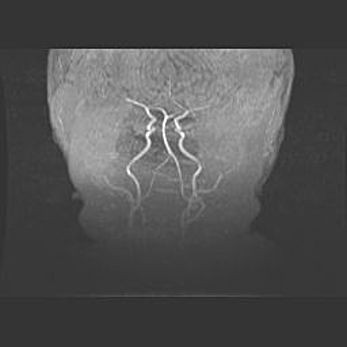

Открытая гидроцефалия.

Возраст: 9 месяцев 12 дней

Вес: 6800 г

Пол: мужской

Окружность головы: 41,5 см

Срок гестации: 28 недель

Гидроцефалия головного мозга у новорожденных имеет характерный признак: опережающий рост окружности головы приводит к визуально хорошо определяемой гидроцефальной форме сильно увеличенного в объёме черепа. Детские неврологи определяют следующие симптомы гидроцефалии у грудничков: выбухающий напряжённый родничок, частое запрокидывание головы, смещение глазных яблок к низу.